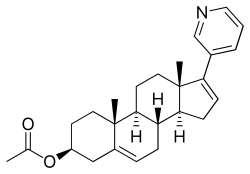

Abiraterone acetate, also known as 17-(3-pyridinyl)androsta-5,16-dien-3β-ol acetate, is a synthetic androstane steroid and a derivative of androstadienol (androsta-5,16-dien-3β-ol), an endogenous androstane pheromone.[41] It is specifically a derivative of androstadienol with a pyridine ring attached at the C17 position and an acetate ester attached to the C3β hydroxyl group.[41] Abiraterone acetate is the C3β acetate ester of abiraterone.[41]